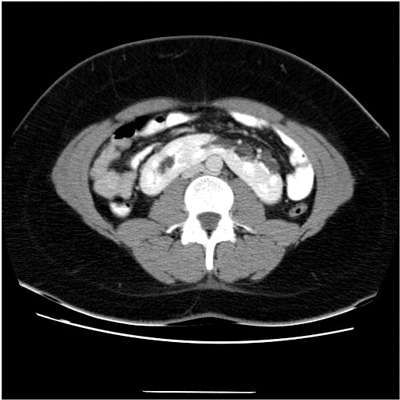

Figure 4: CTU shows fusion of both kidneys on one side of the abdomen.

Crossed fused renal ectopia

In crossed fused renal ectopia (CFRE) the two kidneys are fused and unilateral (Figure 4). In 10-15% of cases the kidneys are not fused. Most commonly the crossed kidney is inferior to the resident, with the upper pole fused to the lower pole of the resident kidney. There are a number of further positional variations, the crossed kidney can also be described as sigmoid, lying inferiorly, L-shaped or S- shaped. A further subtype is when the kidneys are completely fused, forming a large irregular ‘lump’. The kidneys may also be described as ‘pancake’; in this case the kidneys are fused along the medial concave border [1,10].

CFRE occurs in approximately 1 in 1000 births and has a 3:2 male predominance. More than 50% of patients with crossed fused renal ectopia and a third of those with horseshoe kidney have other congenital anomalies, including urogenital, gastrointestinal, cardiopulmonary, skeletal, neurological and chromosomal disorders [8]. CFRE may be an asymptomatic incidental finding. However, patients may present with signs and symptoms of obstruction, urolithiasis, reflux, or infection. These are secondary to the associated abnormalities of megaureter and urethral valves and aberrant arteries (causing ureteric obstruction). Multicystic dysplasia is also an associated abnormality [8].

On the plain abdomen film the soft tissue outline of the kidney may be visible on the opposite side, and there may be malposition of colon into the empty renal fossa [3]. On ultrasound anterior or posterior notches in renal parenchyma may be seen. The renal sinuses will lie in different planes, run in different directions, and reflect echoes differently. CT provides the best diagnostic imaging. The parenchymal band joining the two kidneys can be better visualised on CT and the anatomical relationship with adjacent structures and positions of the ureter can be better assessed. Angiography highlights the anomalous blood supply arising from vessels within the vicinity [8].